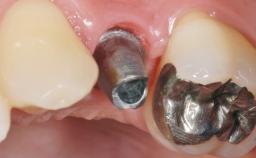

In the fall of 2003, a female patient was referred to the School of Dental Medicine, University of Geneva, for treatment of a traumatic fracture of a maxillary left lateral incisor. While at home, the patient fell down and hit a heating radiator with the anterior maxilla. During the initial examination, a week after the accident, the patient was in good general health condition and signs of pain/discomfort or clinical/radiographic infection were not observed. A moderate and localized hematoma with associated swelling persisted on the left side of the upper lip. Clinical assessment revealed a horizontal fracture at the cervical third of the anatomic crown of the maxillary left lateral incisor. In addition, a vertical crack line projecting into the cementoenamel junction (CEJ) called for a comprehensive assessment of the tooth restorability options.